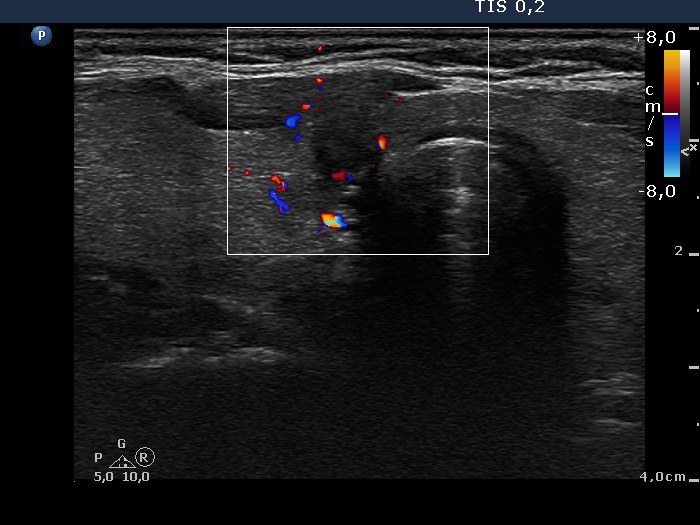

Extrathyroidal spread - case conp 014 (ultrasonographic picture 5)

Medial part of the right lobe, transverse scan, color Doppler mode. The lesion displays signs of intranodular blood flow.